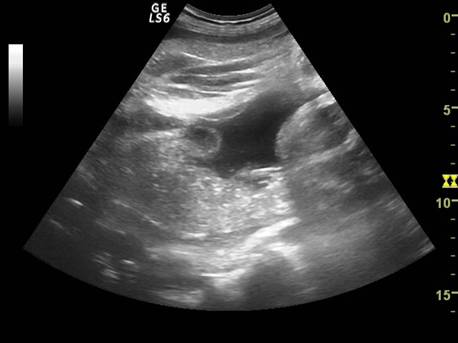

Fig nr. 240.

Edem tegumentar al coapsei ( sageata ) aparut la maceratie, aceeasi sarcina ca

in figurile anterioare